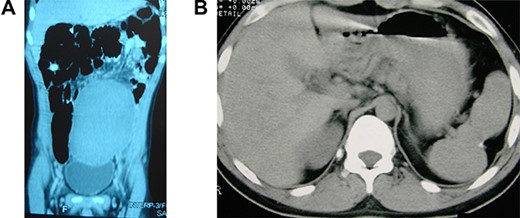

A 14-year-old boy was referred to our hospital due to a long-term history of lower abdominal pain associated with dysuria, tenesmus and constipation associated with a visible tender pelvic mass. He also exhibited a retarded growth (152 cm in height) and sexual underdevelopment characterized by lack of sexual maturity and absence of secondary sexual physical appearance with no facial, pubic and axillary hair growth. Laboratory exams indicated a reduced platelet count of 114 × 103/μl, a white blood cell count of 6.2 × 103/μl and a hemoglobin level of 11.2 g/dl. An axial CT showed the absence of the spleen in the left subphrenic space and an enlarged spleen, measuring 22 × 16 × 13 cm, within the pelvic region (Fig. 1A).

Wandering and twisted splenomegaly. (A) CT scan of the abdomen showing a displaced ectopic spleen in the left flank and pelvic region, characteristic of a wandering spleen. Observe the absence of the spleen in the left hypochondrium. (B) The spleen after detorsion and splenopexy in the left hypochondrium. Observe the reduction of the spleen to a normal size four years after the splenopexy.

The patient had an uneventful recovery and was discharged from the hospital on the second postoperative day. The most significant body growth occurred during the first 9 months after the surgery, and at 18 years of age, he had grown to 183 cm in height, similar to his family size. Together with the body height, all sexual characteristics were improved to normal aspects short time after the splenopexy. All laboratory exams had returned to normal, including a platelet count of 280 × 103/μl, a white blood cell count of 6.4 × 103/μl and a hemoglobin level of 14.9 g/dl. A new CT image demonstrated an almost normal spleen (14 × 12 × 10 cm) with no splenic or abdominal disorder (Fig. 1B). After four years, the patient is still in good health with a normal life, with no complaint related to the surgical procedure.

Even without knowing the mechanism of the dwarfism associated with splenomegaly, total or partial splenectomy performed before the epiphyseal consolidation is generally followed by body and sexual development that runs in line with family characteristics [1–4]. The same good results are achieved if a congestive splenomegaly is treated by releasing the venous blood flow from its obstruction. In this case report, the splenic detorsion improved the venous blood flow and the congestive splenomegaly was reduced to a normal splenic size [9–13, 15] (Fig. 1). Thus, this report demonstrates that dwarfism due to a congestive splenomegaly should only be treated aiming at an appropriate venous blood flow.